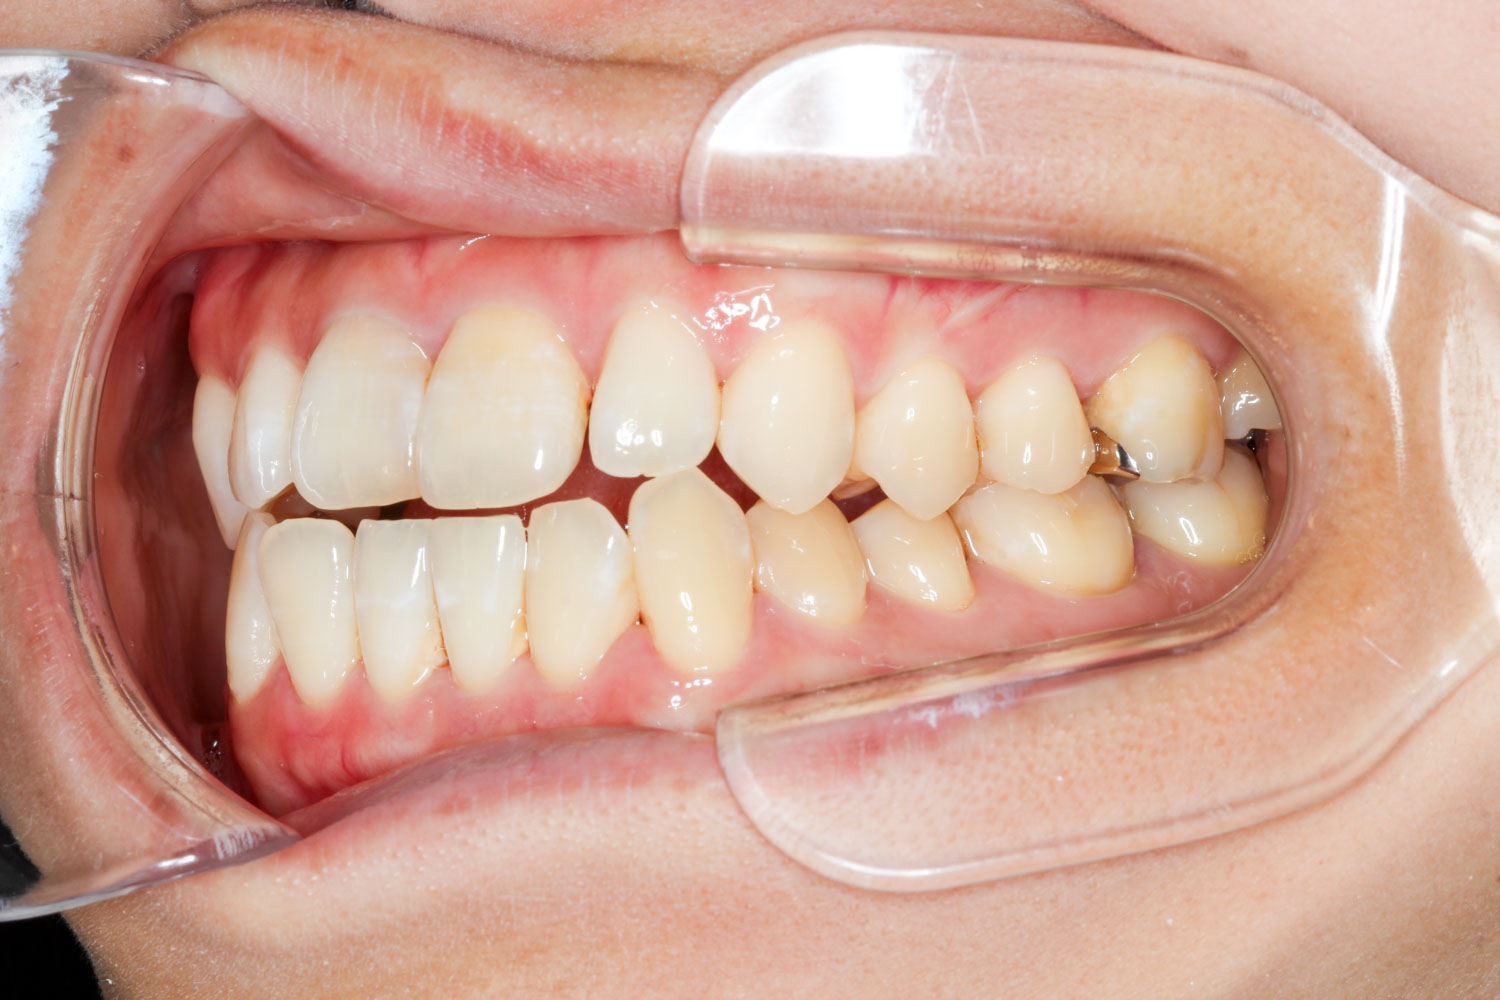

Before

After

年齢 10代

治療装置 表側の矯正装置(ホワイトコース)

治療内容 上下左右4本抜歯

治療期間 2年1か月

リスク 歯の移動に伴う痛み、歯肉退縮、歯根吸収、歯肉炎、虫歯

主訴 ガタガタが気になる

症状 叢生(ガタガタ)

治療回数 25回程度

総額費用 105万円程度